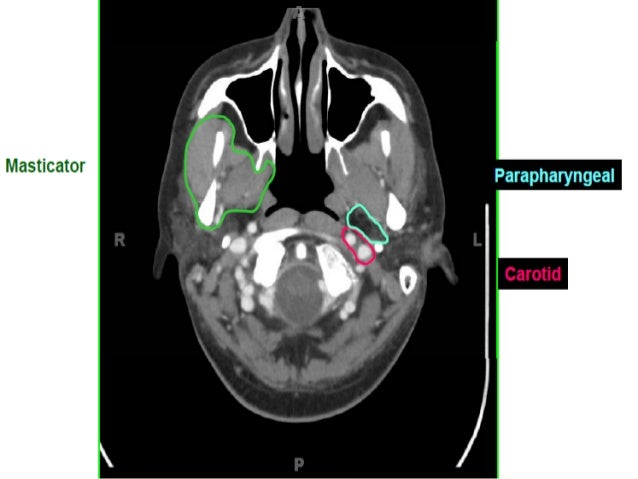

This video is from our cross sectional anatomy series. Cranial cross sectional anatomy is very important to know prior to analyzing a head ct.

Ct cross sectional anatomy. Only 9 left in stock order soon. Ct cross sectional anatomy of brain chest abdomen paranasal sinusus neck temporal bone heart slideshare uses cookies to improve functionality and performance and to provide you with relevant advertising. Symmetry is an important concept in anatomy and is almost always present in a normal head ct unless the patient is incorrectly positioned with the head cocked at an angle.

Once the normal structures are identified abnormalities can be detected and a diagnosis may be possible. Cross sectional anatomy timothy f. Cross sectional anatomy ct mri by govind b.

Cross Sectional Anatomy Of The Neck

Cross Sectional Anatomy Of The Neck